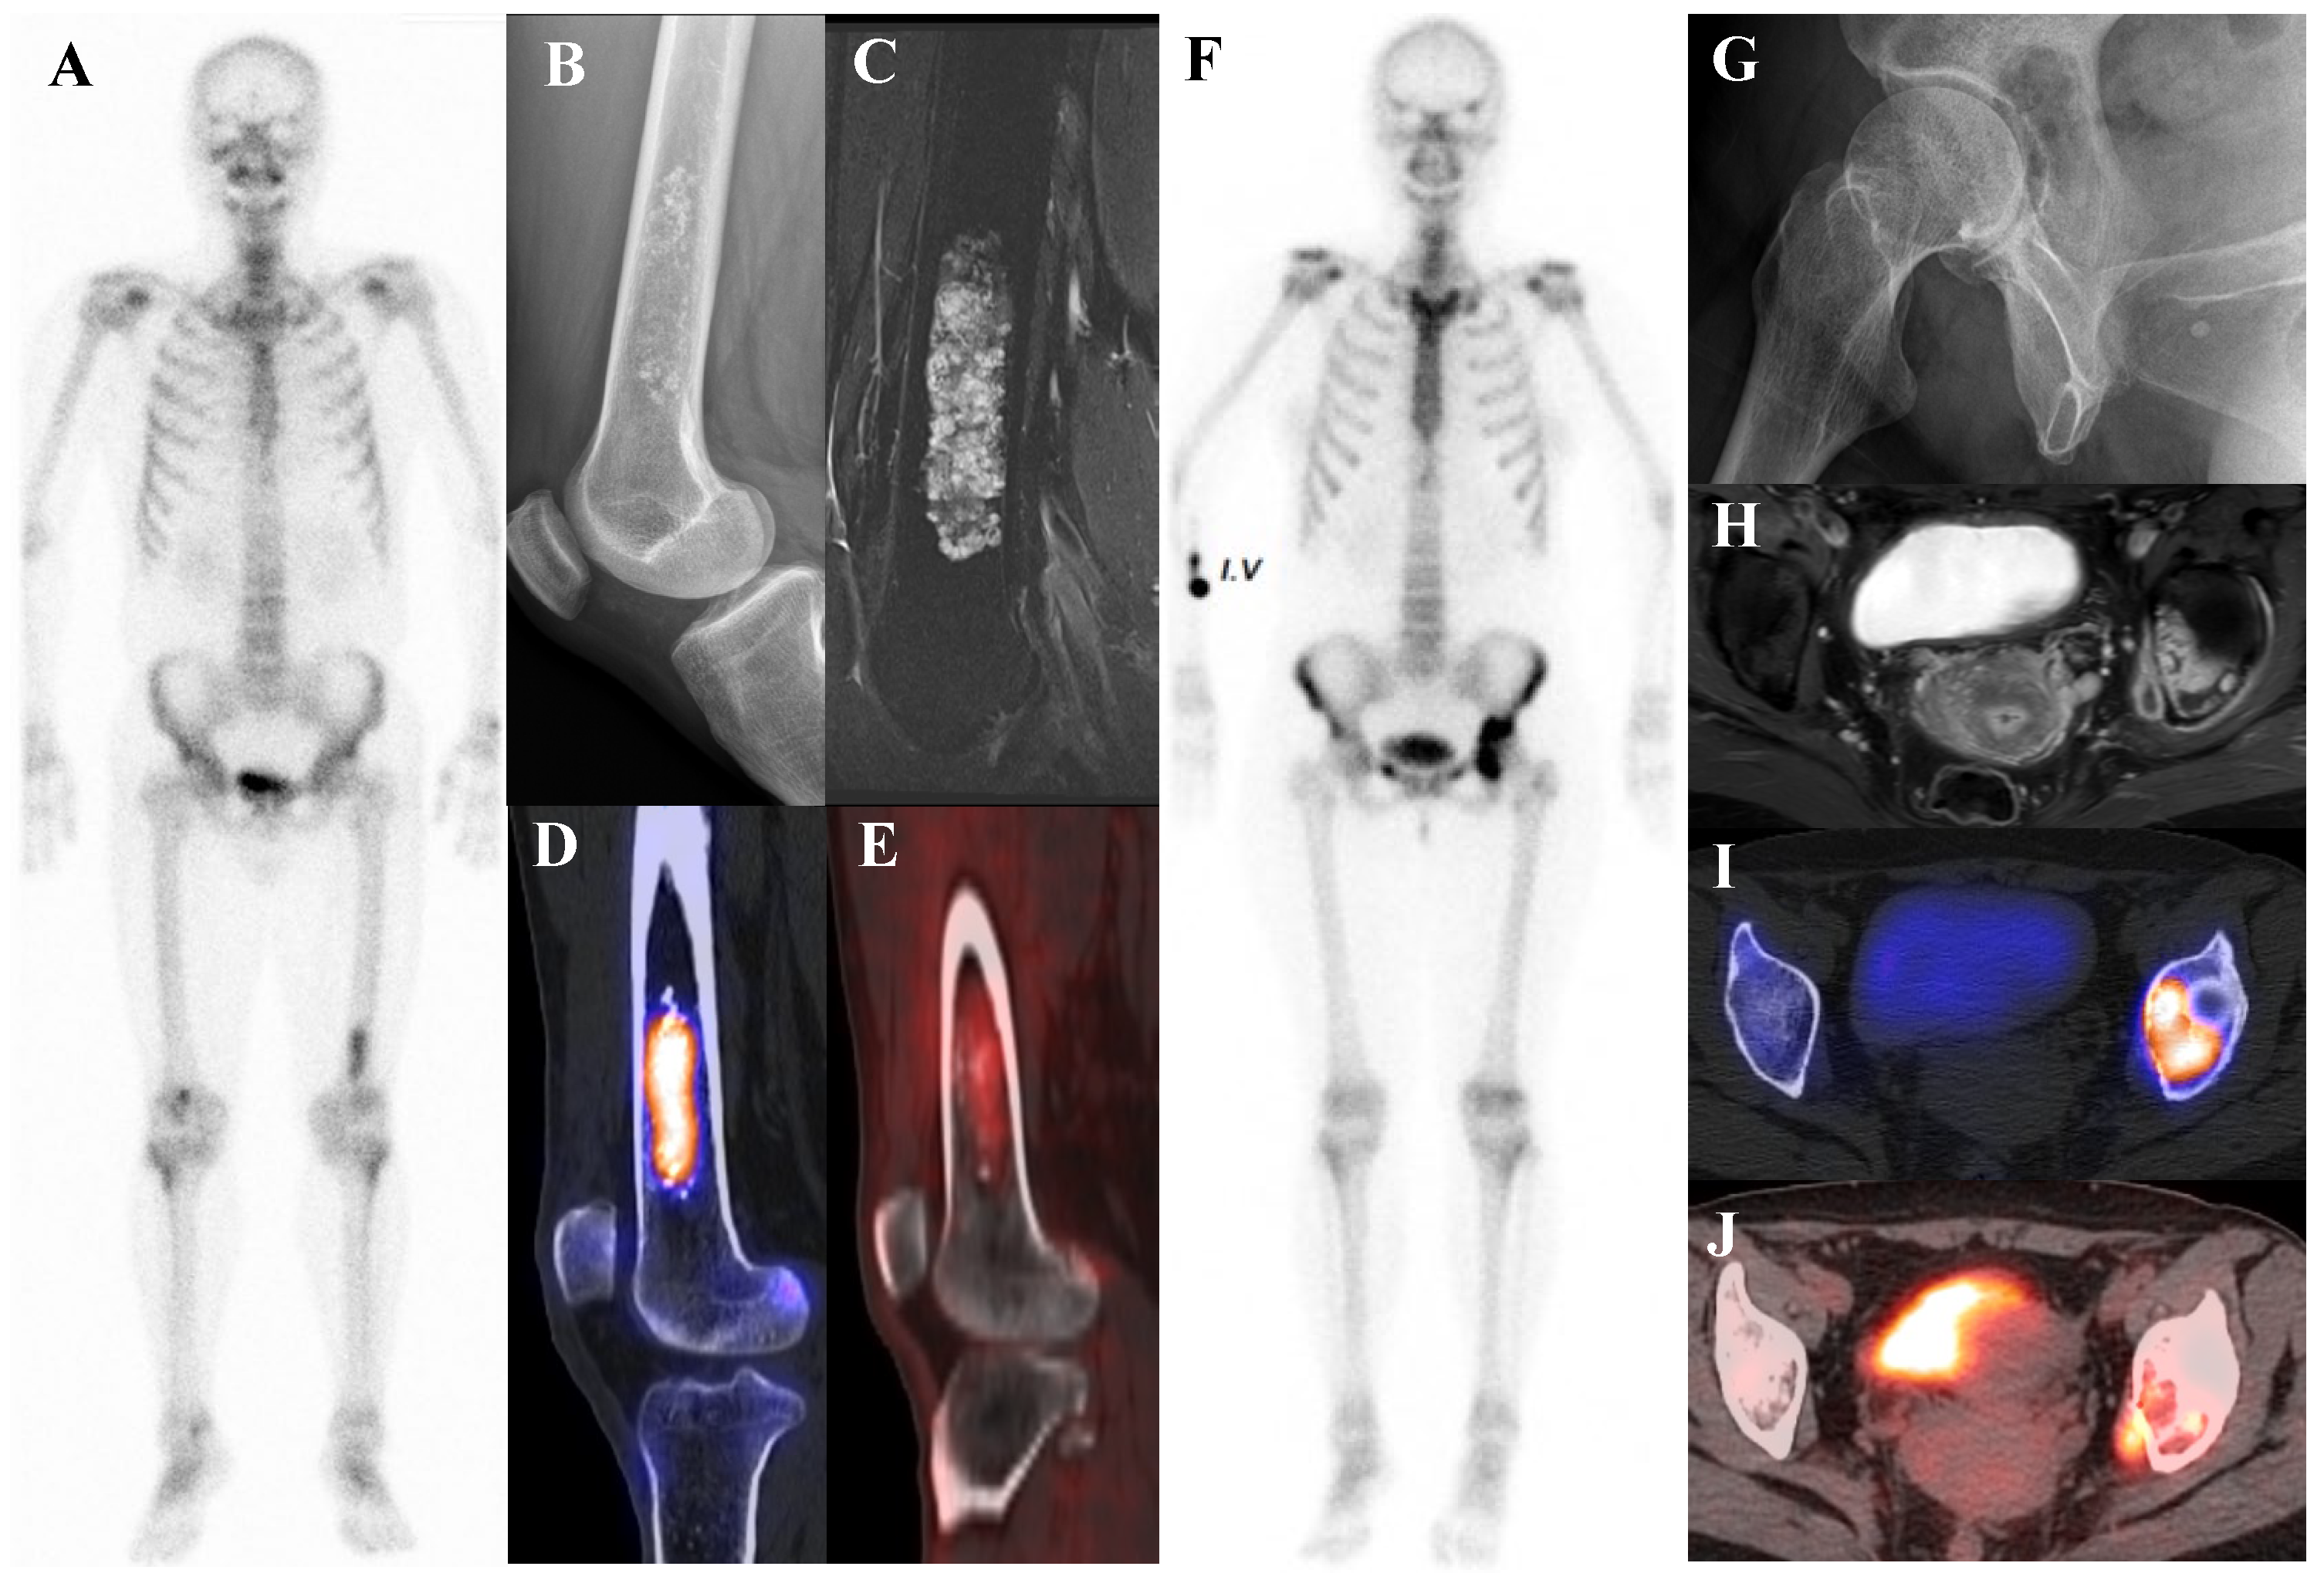

Figure 3 illustrates the spectrum of cartilaginous tumors, from low-grade ACT with mild metabolic activity to high-grade chondrosarcoma with aggressive infiltration and intense uptake, emphasizing the importance of integrating multimodal imaging with histopathology for accurate diagnosis and grading.

Figure 3.

(A–E) A 54-year-old male with atypical cartilaginous tumor (ACT) of the left distal femur. (A) Bone scintigraphy shows increased uptake in the distal metaphysis. (B) Radiograph demonstrates stippled calcifications suggestive of a chondroid tumor. (C) T2-weighted fat-suppressed magnetic resonance imaging (MRI) shows a lobulated intramedullary lesion with heterogeneous signal and equivocal cortical erosion. (D) Bone single-photon emission tomography (SPECT)/computed tomography (CT) demonstrates focal uptake in the distal femur, corresponding to a calcified chondroid mass. (E) [18F]FDG positron emission tomography (PET)/CT shows mild, elongated uptake (SUVmax 2.96) in the lesion with characteristic rings-and-arcs calcification on CT. Surgical excision confirmed ACT. (F–J) A 49-year-old female with high-grade chondrosarcoma of the left acetabulum (F) Bone scintigraphy shows intense uptake. (G) Radiograph demonstrates a geographic radiolucent lesion. (H) T1-weighted fat-suppressed MRI reveals an infiltrative lesion with extraosseous and intra-articular extension, heterogeneous enhancement. (I) SPECT/CT reveals increased uptake in the acetabular region, corresponding to the infiltrative lesion with extraosseous extension. (J) [18F]FDG PET/CT demonstrates intense localized uptake in the left acetabulum with extension into the obturator internus muscle, especially pronounced at the site of extraosseous spread (SUVmax 8.4). Initial biopsy suggested grade I chondrosarcoma; however, wide excision confirmed dedifferentiated chondrosarcoma.